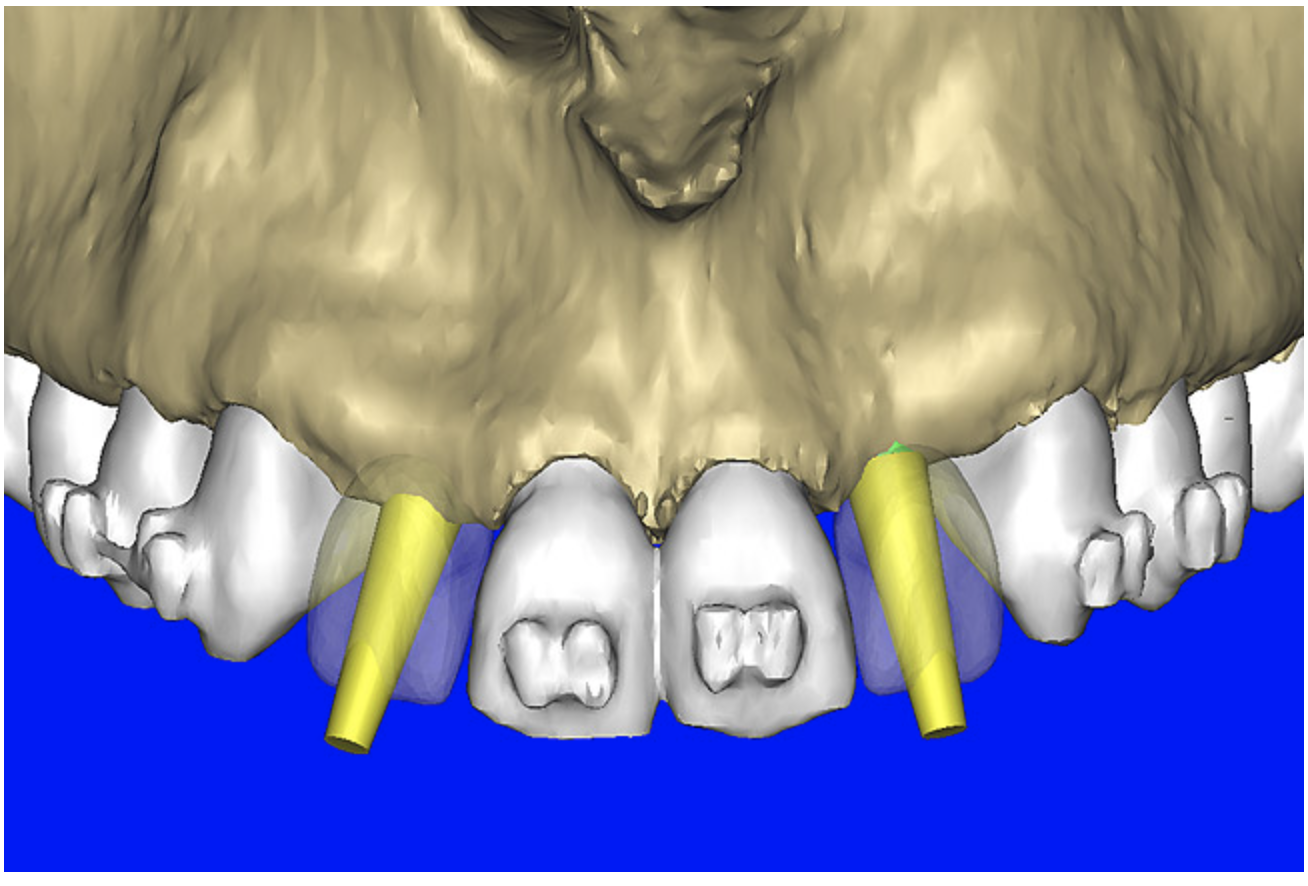

After the basic plan had been established, it was re-evaluated using interactive 3D images. The reconstructed 3D view of the maxilla clearly illustrated the extent of the bilateral facial concavities, and the root eminences of the adjacent and posterior teeth (Figure 7A). The placement of the virtual implants then was evaluated to ensure that the facial cortical plate was not perforated (Figure 7B). The implants were labeled individually as “7” and “10,” with the simulated yellow abutment projection indicating the facial-lingual inclination through the bone to the level above the incisal edge of adjacent teeth. The ability to gain a better understanding of these individual root forms can not be underestimated. The dental literature has suggested certain parameters for placing implants near teeth and implants next to other implants. However, there is little scientific 3D documentation to support these suggested rules.5-10 The use of an interactive treatment-planning software application permits closer scrutiny of previously difficult-to-visualize areas, and can now be used to redefine perceptions of spatial positioning of implants, especially when in close proximity to natural tooth roots, vital anatomy, and adjacent implants.27-29

Figure 7a  The 3D reconstruction showed (A) the facial concavities and root eminences, and allowed (B) for evaluation of virtual implant placement to ensure the facial cortical plate was not perforated.

Figure 7b  The 3D reconstruction showed (A) the facial concavities and root eminences, and allowed (B) for evaluation of virtual implant placement to ensure the facial cortical plate was not perforated.

Figure 7b